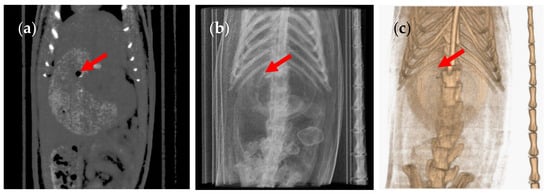

3. Results and Discussion